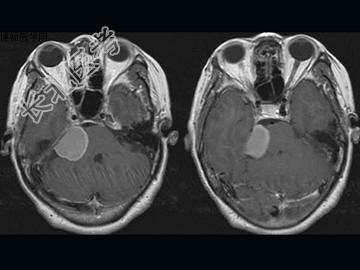

- 单项选择题女,57岁, 左侧听力进行性减退半年余,MRI检查如图, 最可能的诊断为 ( )

A、听神经瘤

B、三叉神经瘤

C、胆脂瘤

D、脑转移瘤

E、桥小脑角脑膜瘤